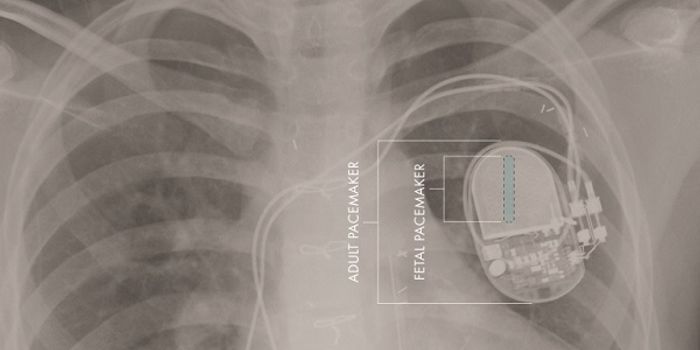

MAR 31, 2015CardiologyA team of investigators at Children's Hospital Los Angeles (CHLA) and the University of Southern California have develop ...

-